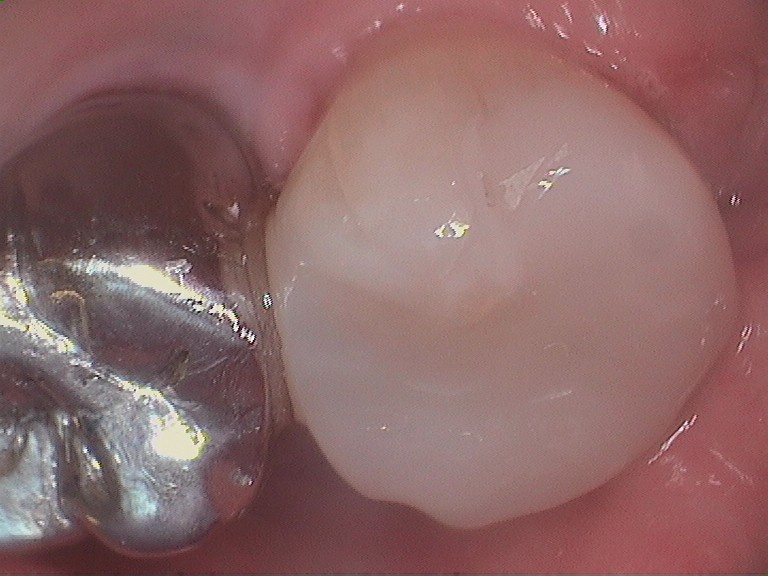

Gallery